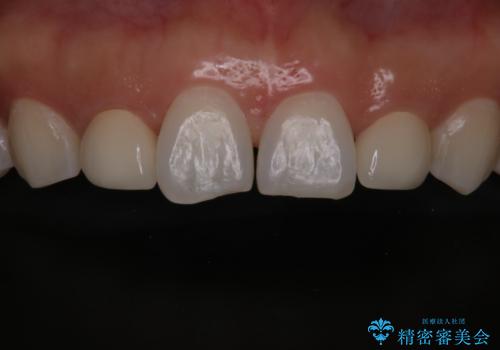

歯の形気になる!! セラミック治療 前歯( エクセレント)

- 歯の形が気になるということで以前入っていたプラスチックのものから、セラミックでの治療を希望されたので行いました。

色や形をこだわりたいということで、当院最上位ランクのエクセレントにて治療を行いました。

患者様はかなり喜ばれておりました。